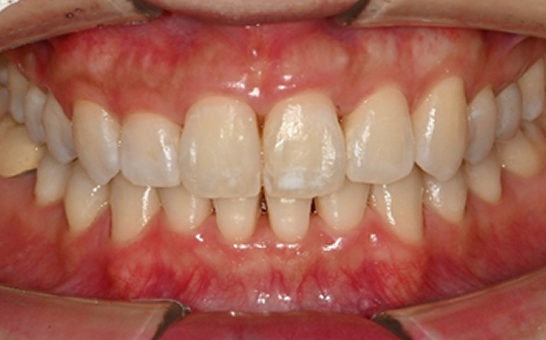

인비절라인 퍼스트(Invisalign First)는 어린이와

성장기 청소년을 위한 투명 교정 장치로, 치아와 턱뼈가

성장하는 과정에 맞춰 설계된 교정 시스템입니다.

해당하는 증상이 있다면 전문의와 상담 후 조기 교정 시

성장기 어린이에게 교합이 틀어지는것을 미리 예방 할 수 있습니다.

※ 바른선택치과의원은 의료법을 준수하며 위 케이스는 실제 내원 환자분의 동의하에 공개된 사진과 동일한 환자분께 같은 조건에서 촬영한 사진을 활용했습니다.

개인에 따라 진료 및 치료 방법이 다르게 적용할 수 있으며, 효과와 부작용이 개인마다 다르게 나타날 수 있는 점을 안내해 드리며, 진료 전 전문의료진과 충분한 상담을 권해드립니다.